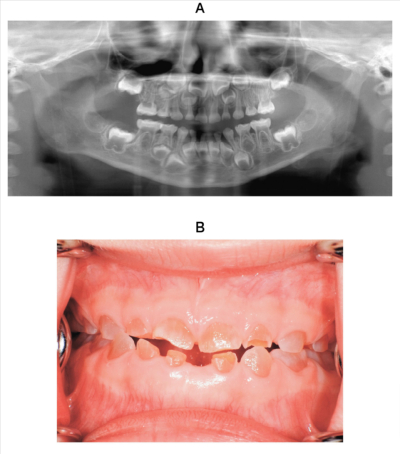

4歳の男児。歯の変色を主訴として来院した。初診時のエックス線画像と下顎左側乳中切歯脱落後の口腔内写真を別に示す。

疑われるのはどれか。1つ選べ。

a. 歯のフッ素症

b. Hutchinson 歯

c. 象牙質形成不全症

d. エナメル質減形成症

e. エナメル質形成不全症